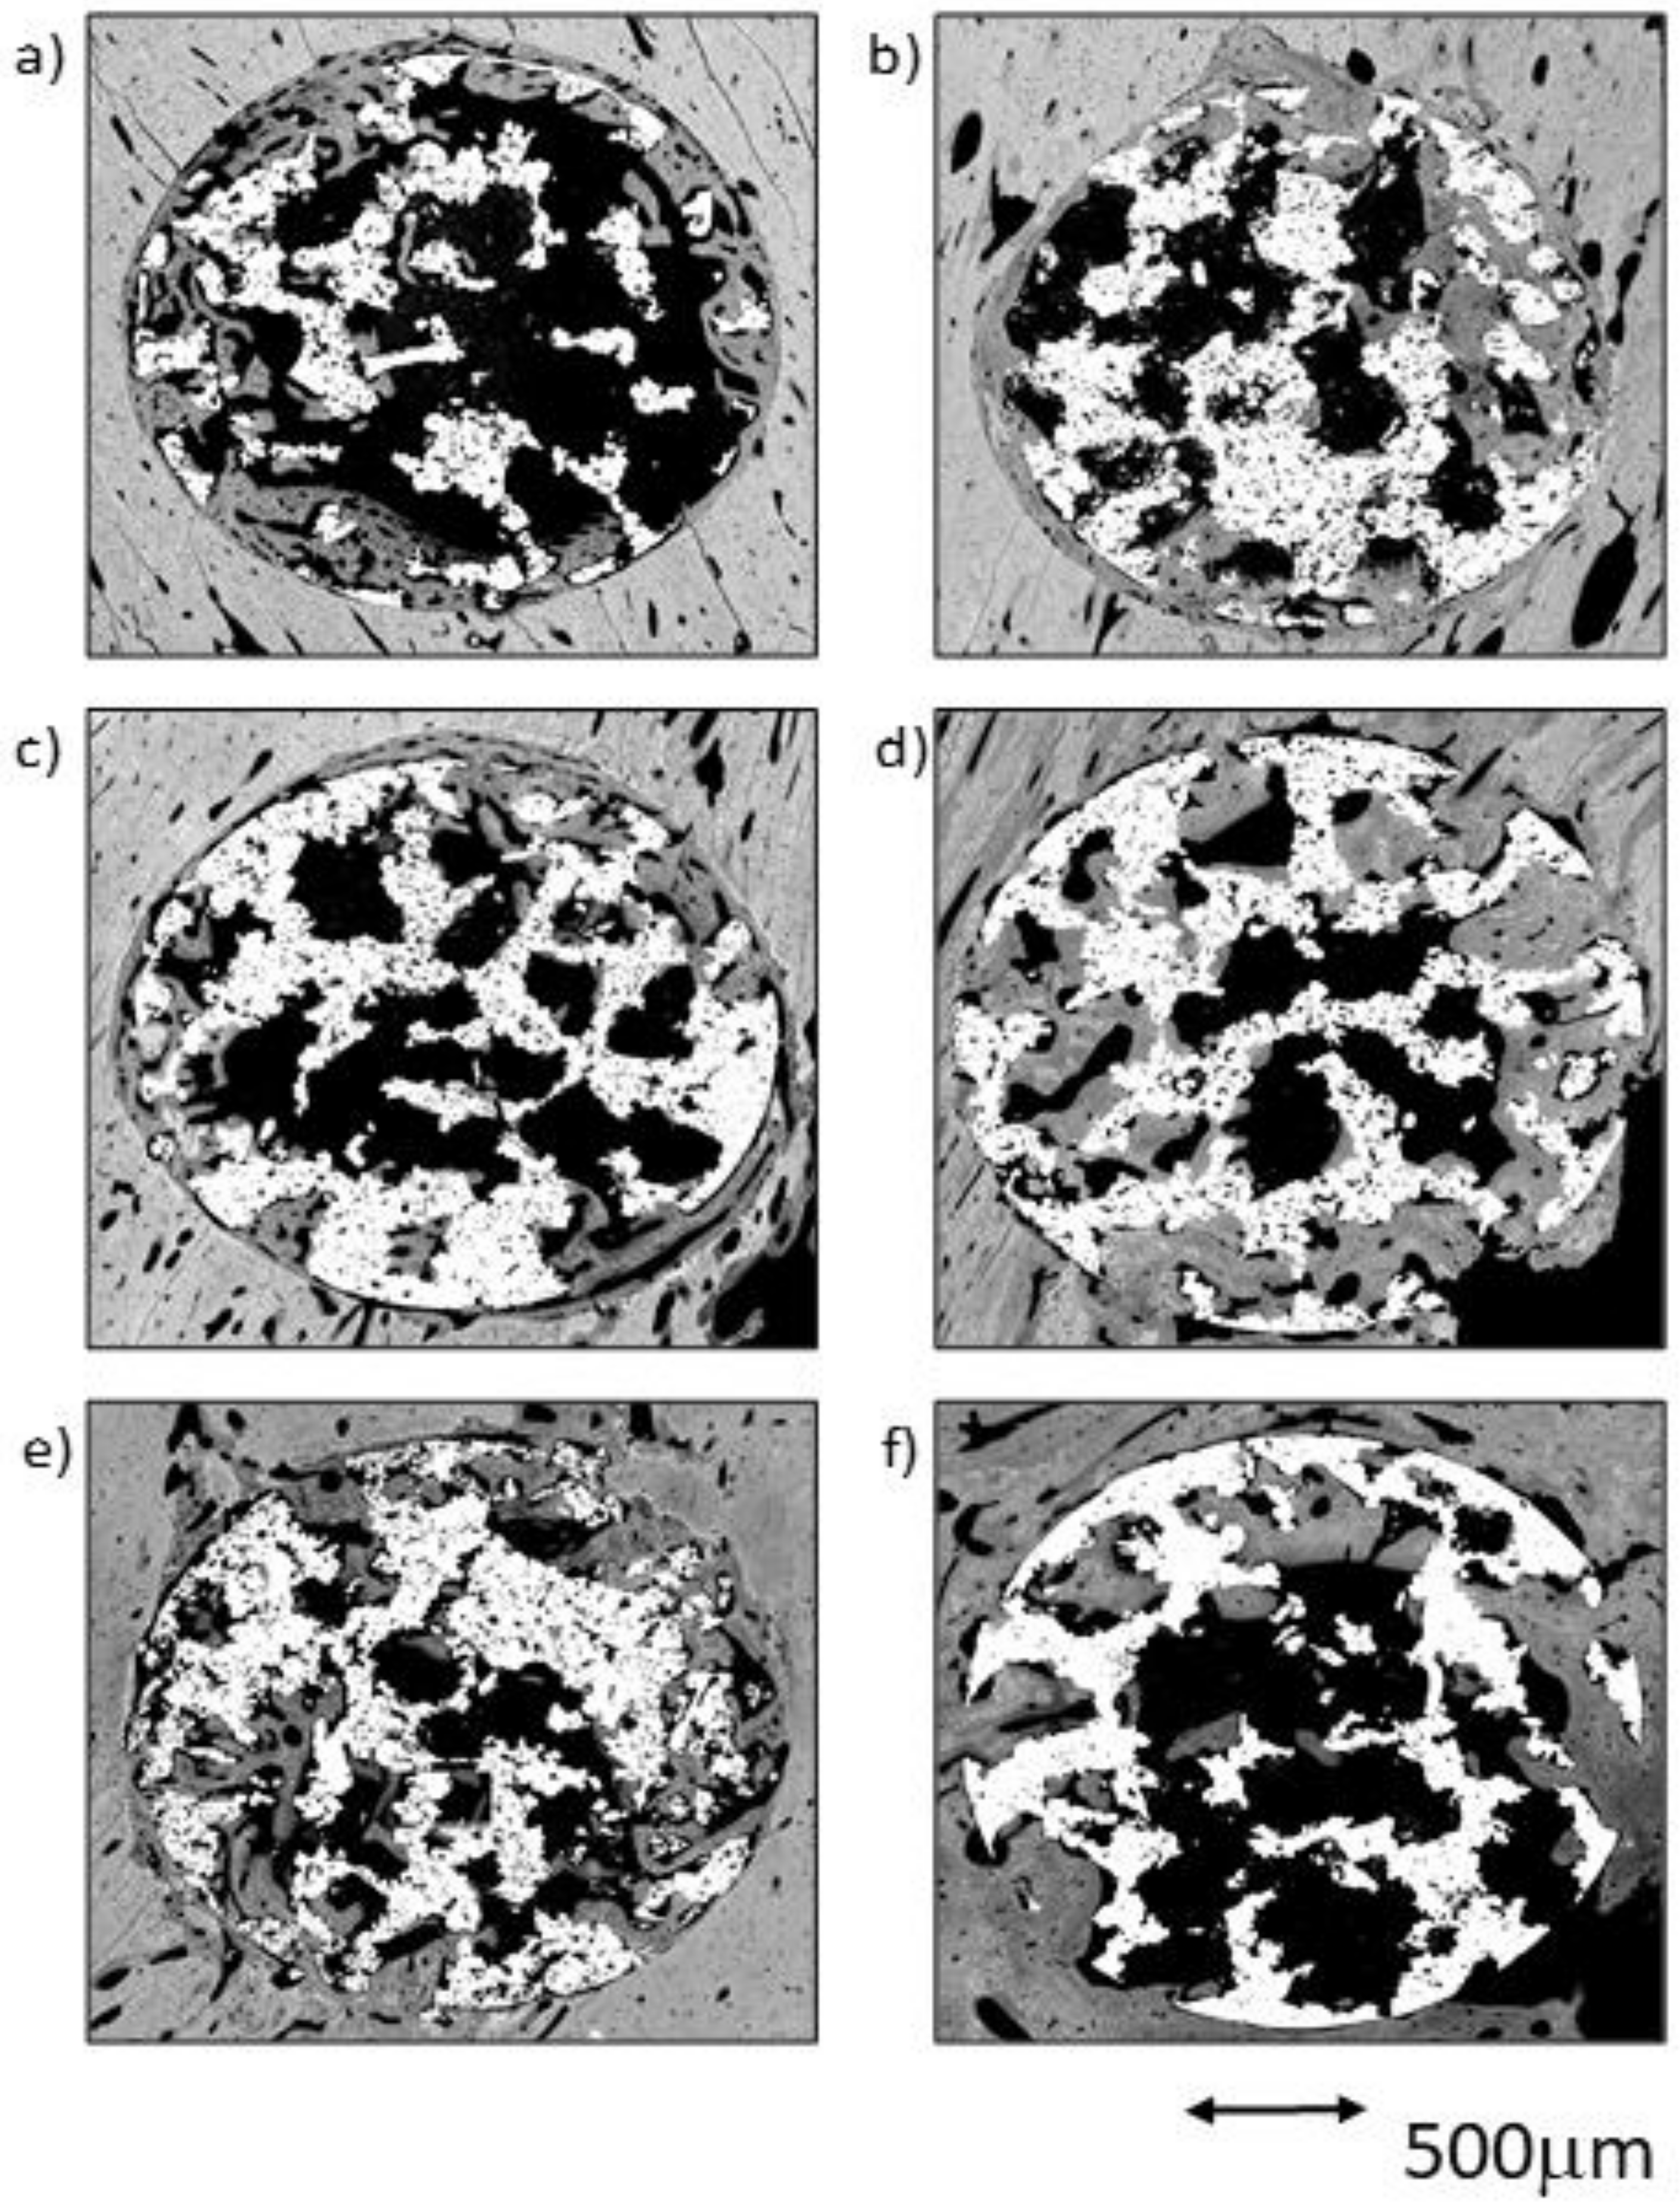

The comparative analysis between the results for all samples in each group from both time points (4 and 12 weeks) reflected an overall tendency for increases in the newly formed bone percentage during the postoperative period. However, an isolated anomaly was observed in TCG (12 weeks), where the newly formed bone percentage in ROI2 slightly decreased 12 weeks after implantation (Table 1). The BSE-SEM micrographs are presented in (Figure 3), revealing the differences in both bone in-growth and bone on-growth as a function of group. In Figure 4, the new in-growth bone formation 4 and 12 weeks after implantation is shown.

Figure 3.

BSE-SEM results 4 weeks (left) and 12 weeks (right) after porous titanium implant insertion in transversal view: (a,b) CG; (c,d) TCG; (e,f) PAG.